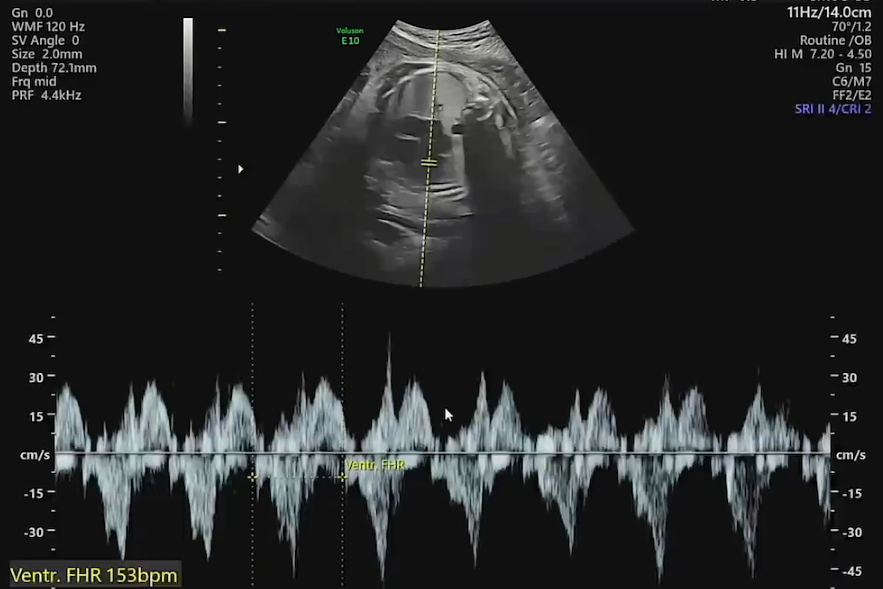

심장도 방방 잘 뛴다(153bpm). 추정체중은 약 2.2kg 정도.

| 31~40주 | 110~150 BPM | 153 bpm(31주 6일) |

| 32주 | 40~42 ㎝ | (FL/6.51) 45.57cm | 1.7 ㎏ | (31주 6일) 2.269kg |